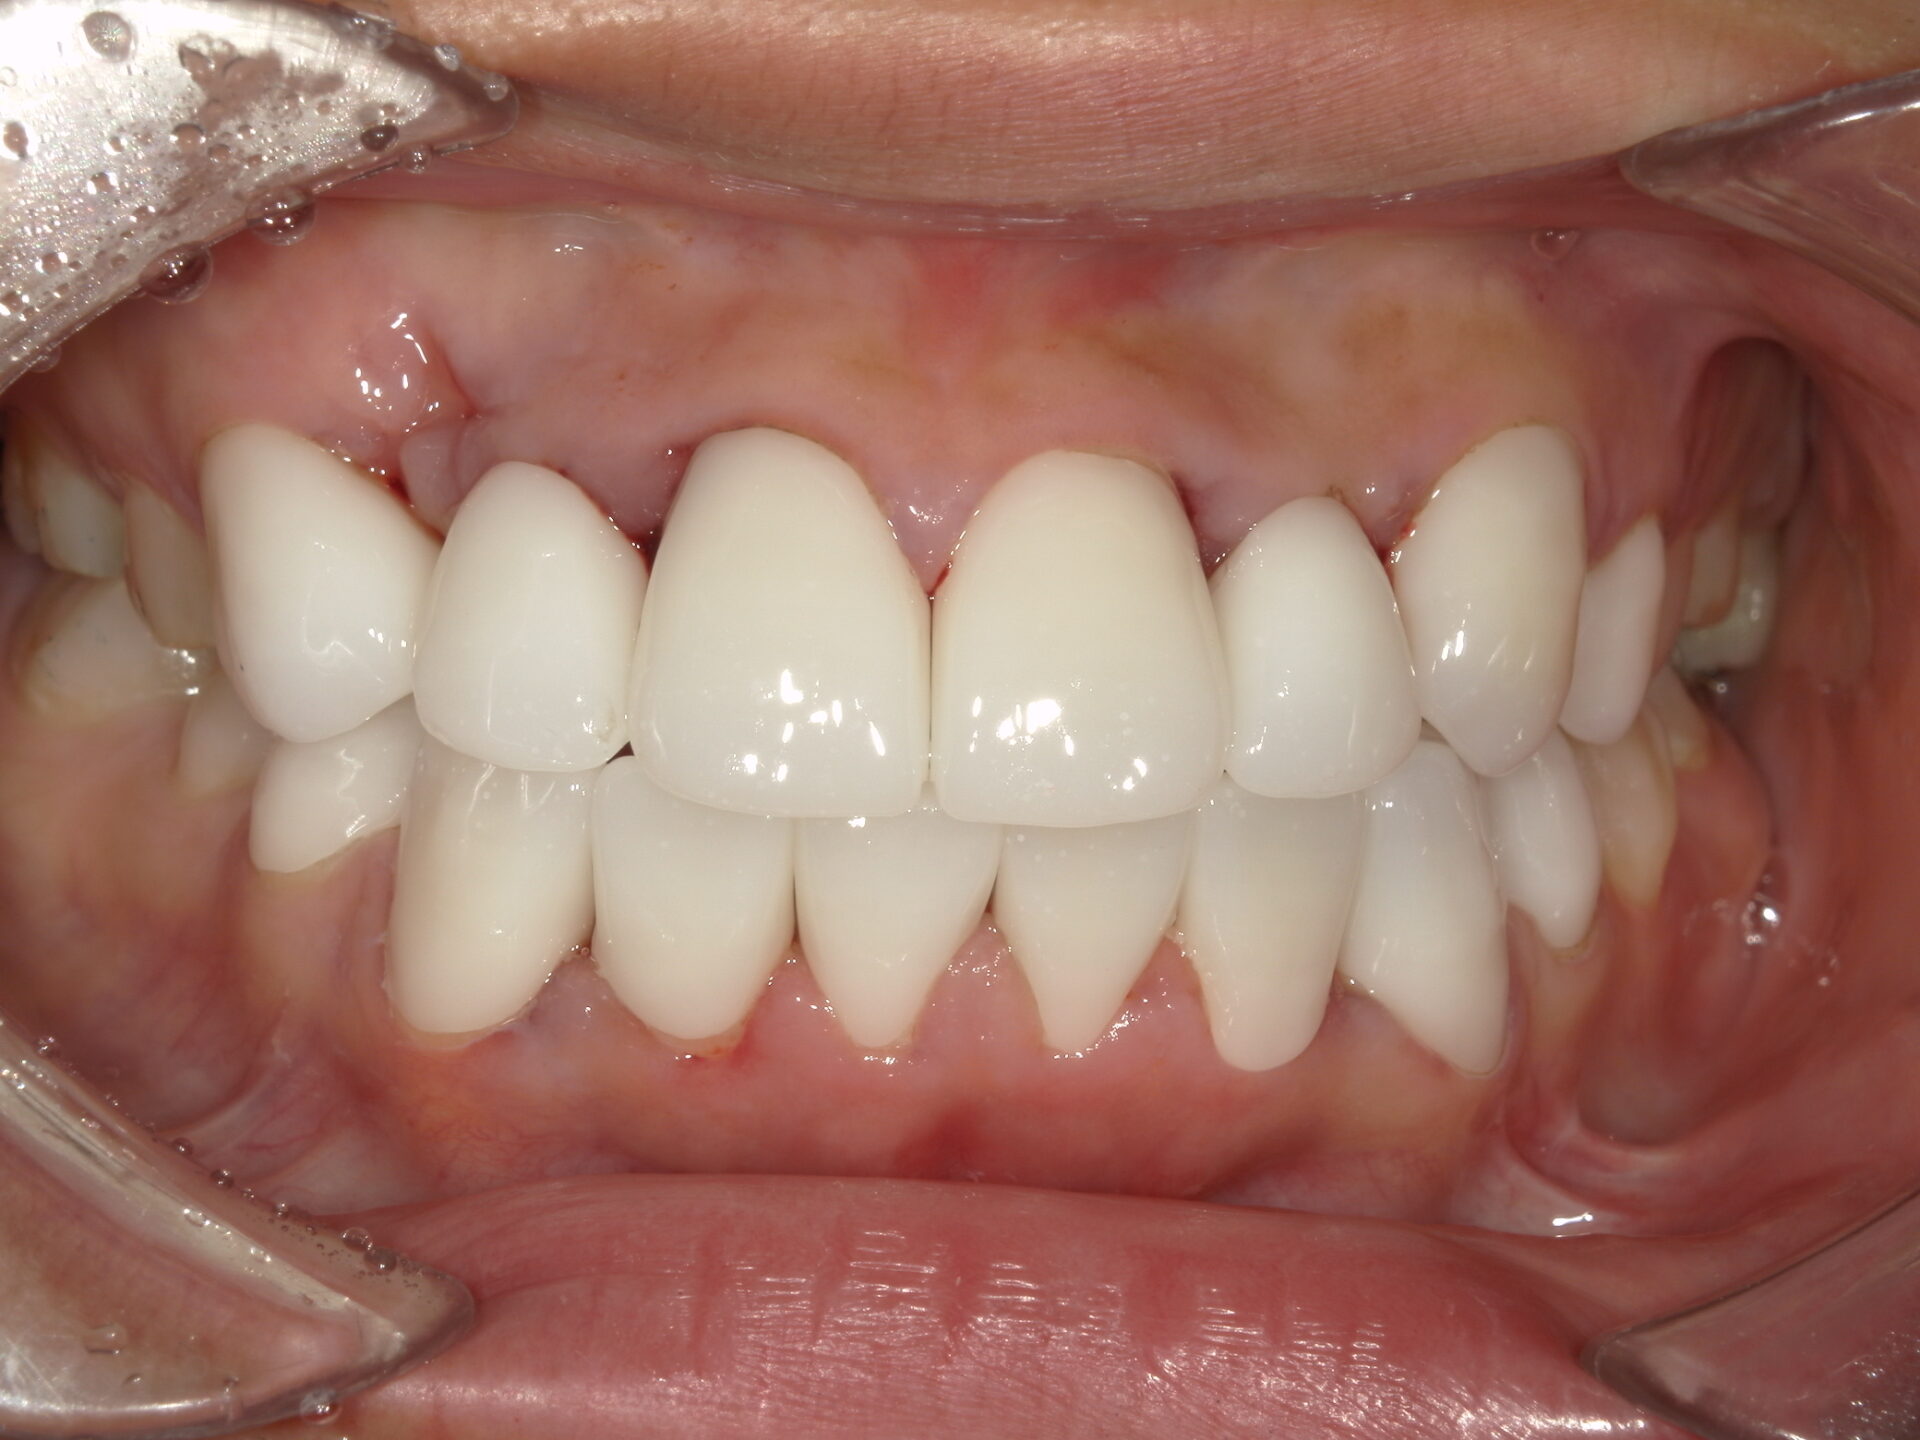

患者さんの年齢 20代 女性 症状 ガタガタを治したい 治療内容 マウスピース矯正治療 費用 90万(税抜) 治療期間・回数 治療期間2年、通院回数10回 メリット 笑顔が綺麗 デメリット・リスク 期間がかかることがある - マウスピース矯正